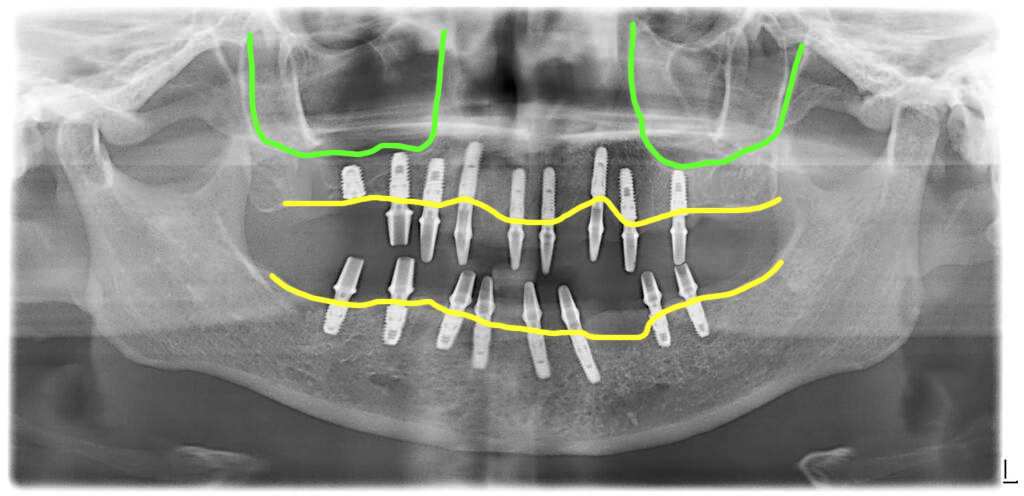

남아있는 치아들을 모두 발치하고 임플란트를 식립했습니다. 위쪽 오른쪽 어금니 부분에는 뼈가 너무 없어서 상악동 뼈이식을 측방접근법(윈도우)으로 시행하면서 임플란트를 식립했어요.

상악동 뼈이식을 하면서 식립한 임플란트는 초기고정이 좋지 않아 지대주를 연결하지 않고 잇몸 속에 묻어 두었고, 나머지의 임플란트에는 지대주를 연결해서 당일 임시치아를 끼워드렸습니다.

잇몸뼈가 많이 무너진 부위는 엑스레이 사진에서 보듯이 임플란트가 더 깊이 식립이 됩니다. 그러므로 치주염이 있는 분들은 가능한 이렇게 잇몸뼈가 많이 내려가기 전에 발치를 해 놓으시는 것을 추천드립니다.